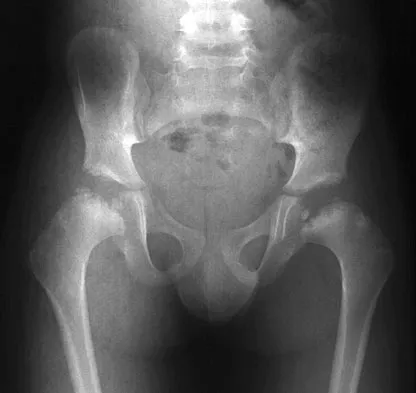

Figure 17 shows the AP radiograph of a 5-year old child who has mild short stature and a painless bilateral gluteus medius lurch. Initial work-up should include

Detailed Explanation

Bilateral flattening of the femoral heads suggests multiple epiphyseal dysplasia; therefore, a skeletal survey is indicated to look for involvement of other epiphyses. Unilateral flattening of the femoral head would suggest Legg-Perthes disease. Sponseller PD: Skeletal dysplasias, in Morrissy RT, Weinstein SL (eds): Lovell and Winter's Pediatric Orthopaedics, ed 5. Philadelphia, PA, Lippincott Williams & Wilkins, 2001, pp 269-270.